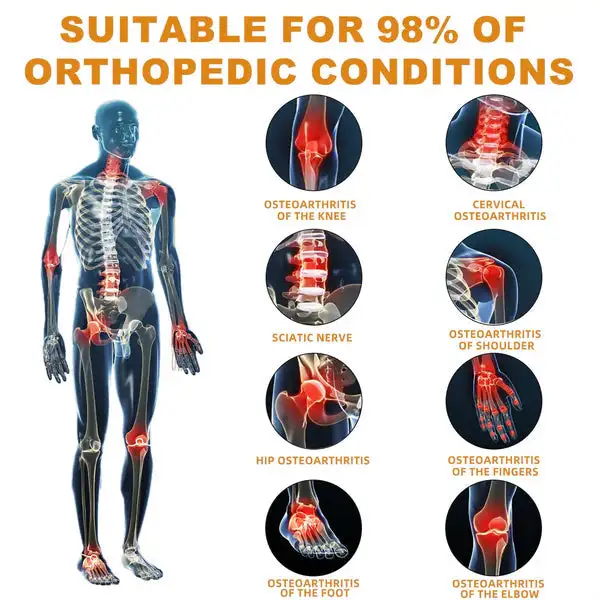

The ArthroFree™ Bee Venom Pain-Relief Bone Healing Cream is celebrated for its efficacy in addressing a wide array of orthopedic conditions. These include osteoarthritis, rheumatoid arthritis, bursitis, tendinitis, osteoporosis, gout, carpal tunnel syndrome, ligament sprains and strains, bunion deformities, and tennis elbow.